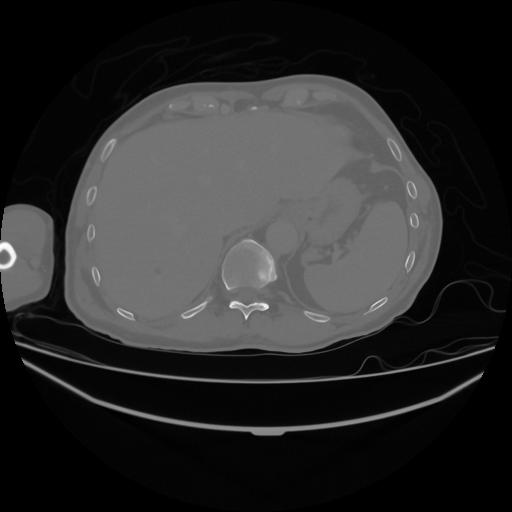

5 CUERPO,CE,Vol,1.0,CUERPO,,